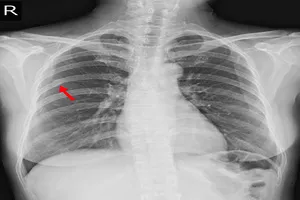

7. 폐렴

폐 조직에 염증이 생겨 발생하는 질환으로, 세균, 바이러스, 곰팡이 등 다양한 원인균에 의해 발생할 수 있습니다. 오른쪽 흉통, 기침, 가래, 발열, 호흡곤란 등의 증상을 유발하며, 흉부 X-ray, 혈액 검사 등을 통해 진단할 수 있습니다. 항생제 투여, 기침약 복용, 충분한 휴식 등 보존적인 치료를 통해 대부분 호전되지만, 중증인 경우에는 입원 치료가 필요할 수 있습니다.